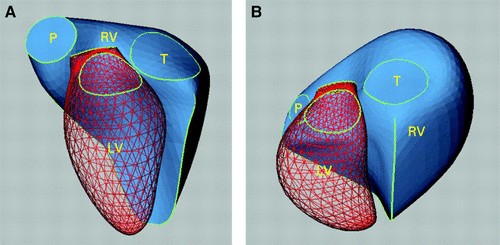

Thất phải có cấu trúc giải phẫu khá phức tạp. Về mặt hình học, thất phải là một khối hình tháp 3 mặt, ôm lấy thất trái. Ở mặt cắt trục dọc thất phải có hình tam giác, ở mặt cắt trục ngang có hình lưỡi liềm (hình 1). Thành tự do TP mỏng (2-3 mm), mềm, có độ đàn hồi cao. Cơ thất phải được tạo bởi các sợi cơ vòng ở lớp nông bên ngoài phía thượng tâm mạc và các sợi cơ dọc ở lớp sâu bên trong phía nội tâm mạc. Các sợi ở bề mặt bao vòng quanh thất phải và liên tục với các sợi cơ ở lớp nông sát thương tâm mạc của thất trái. Các sợi cơ dọc ở lớp sâu chạy dọc từ đỉnh đến đáy của tim. Thất phải co lại theo ba hướng: chuyển động vào trong buồng tim của thành tự do thất phải, sự co ngắn lại của các sợi dọc kéo mỏm tim về phía đáy của tim và lực co của thất trái. Sự co ngắn của các sợi cơ dọc đóng góp một phần lớn vào hiệu suất tâm thu của thất phải, thành phần co của thất trái đóng góp khoảng 20-40% cung lượng của thất phải [14].

Hình 1. Hình thái thất phải (RV) bình thường và bệnh lý- hình ảnh tái tạo 3D.

A- Hình thái phức tạp của thất phải ở tim bình thường. B- Tái cấu trúc thất phải gây giãn thất phải do quá tải mạn tính về thể tích hoặc áp lực trong thất phải.

(phần lưới màu đỏ là tâm thất trái (LV) và phần màu xanh đặc là thất phải (RV), P- Van ĐM phổi; T - Van ba lá). Nguồn: Sheehan và Redington